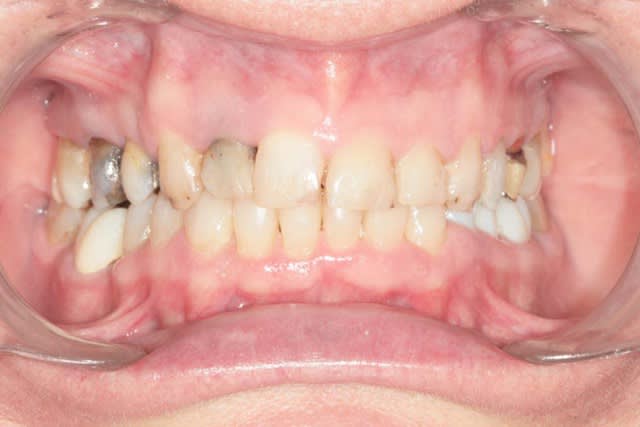

Récemment Céramik râlé, parce qu'il n'y avait pas de nouveau cas (esthétique je crois) à se mettre sous la dent. Je me jettes à l'eau avec ce dernier cas posé ce vendredi (y'a pas plus frais), une larme à l'oeil parce qu'il s'agit aussi du dernier gros cas dans mon cabinet que je quitte cette semaine pour rejoindre ma belle et nos p'tits bouts loin la bas dans le sud.

La patiente a un sourire très médiocre avec migration de plus en plus marqué du bloc incisivocanin sup. Comment l'aidez vous?